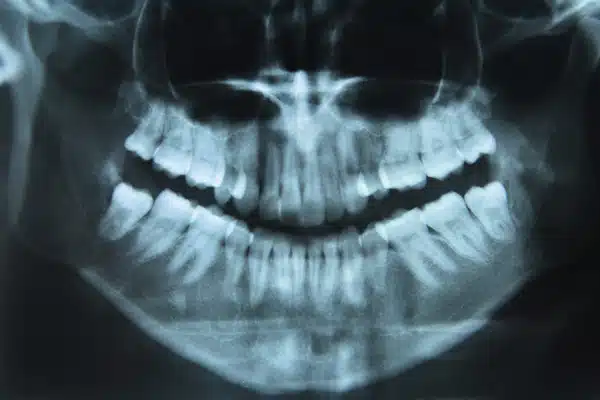

Every patient’s mouth is different, just like every patient’s reason for having crooked teeth may be different. There are a lot of causes for crooked teeth, and any one or combination of these reasons may trigger patients to seek orthodontic treatment near Warren, NJ at Smiles by Lorino Orthodontics. For example, crooked teeth can be caused by:

These factors will result in teeth that are misaligned, overlapping, angled, or growing in improperly. In addition to being visually unappealing, teeth that grow in this way may be putting patients at risk for oral health problems near , as bacteria, sugar, and food can get trapped in the misshapen spaces between teeth, and proper brushing and flossing becomes difficult or even impossible.